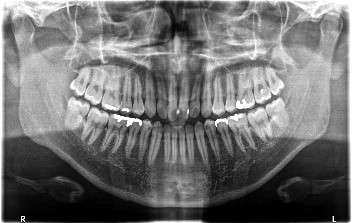

口腔内の状態を記録、診断し、治療計画を立てるために撮影します。

患者さん自身の口腔内の状態を視覚的に示すことで、歯周病治療の重要性を理解しやすくします。

歯の状態や、歯を支える歯槽骨の状態、骨吸収の範囲と程度を検査します。